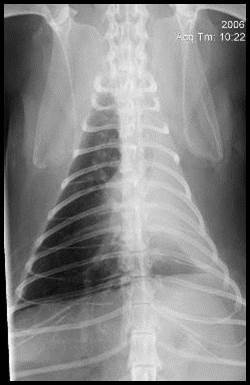

VD/DV view

Displacement of the midline structures due to increased or decreased volume of adjacent structures, e.g. mass, fluid or lung collapse.

Reduction in volume – normal structures move towards the area of a problem

Pic – left lung collapsed, so mediastinum and cardiac silhouette has moved towards it